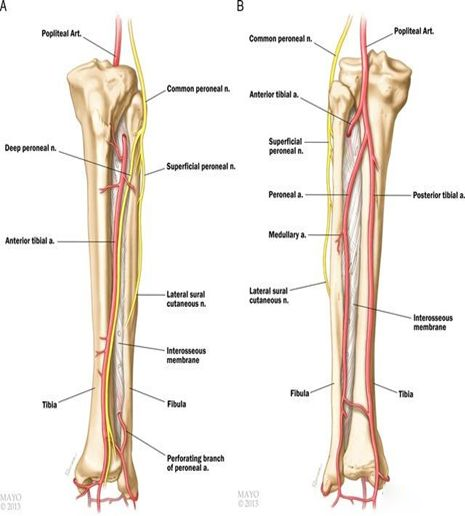

解剖生理

1、胫骨略向外弯,有12-15度生理弧度,骨干的上2/3呈三棱形,下1/3逐渐变为四方形,中下1/3交界处相对较细,是骨折的好发部位。

2、胫骨前内侧无肌肉附着,仅被皮肤覆盖,骨折移位大者,易刺破皮肤,造成开放性损伤。

3、胫骨上1/3后方有腘动脉及其分支胫前动脉、胫后动脉通过;腓骨小头的内下方有腓总神经通过,该部位骨折,有可能损伤血管和神经。

4、胫骨的滋养动脉于上1/3后方进入骨皮质下行,支配中、下段血供,因此胫骨中下段骨折,血供破坏,可发生迟缓愈合或不愈合。